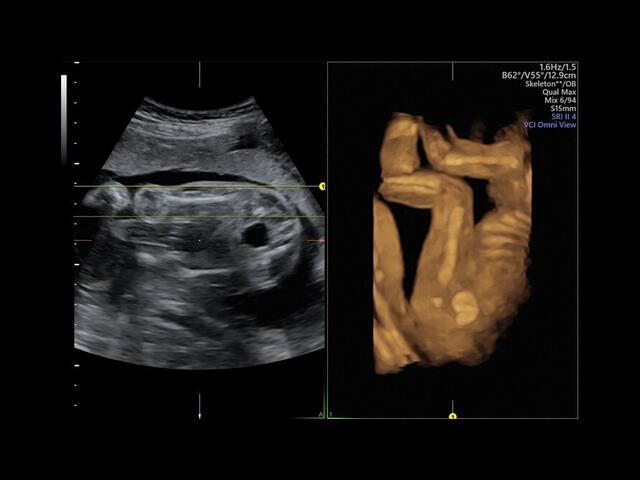

Система GE Voluson E8 обладает значительной вычислительной мощностью, которая позволяет решать даже самые сложные задачи в области диагностики плода. Она отличается высоким уровнем качества и статусом, предоставляя врачу потрясающие изображения во время 2D/3D-исследований. Кроме того, система всегда готова к использованию режима 4D благодаря чувствительному цветному доплеру.

• HDlive: Технология HDlive обеспечивает анатомический реализм и высокую точность диагностики, позволяя совмещать несколько независимых источников света для создания оттенков и теней.